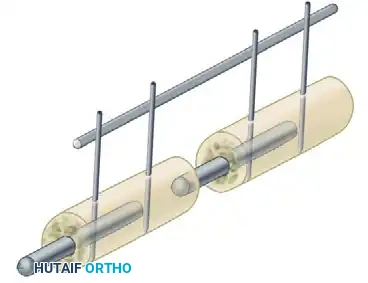

The rigidity of an external fixator construct is determined by several modifiable variables:

* Pin Spread: Increasing the distance between the two outermost pins in a single bone segment increases the stability of the construct.

* Number of Pins: Increasing the number of pins per segment increases stiffness, though the biomechanical advantage diminishes after three or four pins per segment.

* Number of Bars: Adding a second longitudinal bar (creating a stacked or double-bar construct) significantly increases stiffness, particularly in bending and torsion.